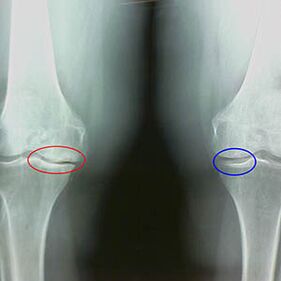

A determinación do grao de artrose prodúcese por x -rayrevelando a participación no proceso patolóxico das estruturas óseas. O seu cambio indica que o sistema muscular leva 5-10 anos dun desequilibrio. Por regra xeral, a xente Durante varios anos experimentan dores dores.

Características de raios x e da segunda etapa da artrose do xeonllo:

- os bordos apuntados dos tubérculos inter -crib na tibia, onde está unido o ligamento en forma de cruz;

- estreitamento da brecha articular no lado medial;

- Os bordos apuntados dos condilos de ósos nos lados mediais, menos frecuentemente en lateral, dependendo do desenvolvemento da deformación do valgus ou da articulación varior.

Para a segunda etapa en Larsen É característico o estreitamento da brecha conxunta en máis dun 50%, pero isto só se pode comprobar en dinámica ou comparación cunha articulación diferente.

A radiografía mostra a presenza de osteófitos, un cambio no espazo entre os ósos femorais e a tibia, o que indica a perda de cartilaxe no xeonllo. Ás veces, o x -rancia das articulacións do xeonllo mostra signos significativos de desgaste da cartilaxe, pero os pacientes non experimentan dor significativa.Pola contra, a artrose da primeira etapa pode interromper a función do xeonllo, xa que a causa da dor son os músculos hipotónicos.